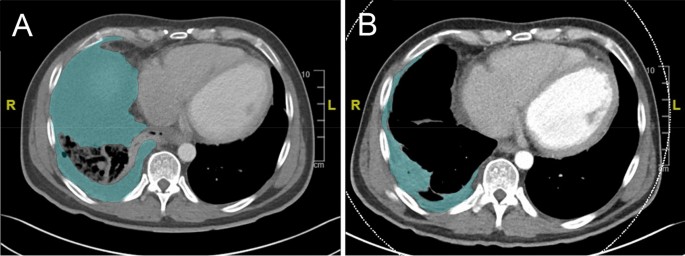

CT volumetric analysis

Computed tomography scans were performed on a clinical 64-detector CT scanner, mostly in the portal venous phase (80% portal venous, 12% native, and 8% arterial). The data were reconstructed in the transverse plane with a slice thickness of 1 mm and an increment of 1 mm. Volumetry was performed by an experienced radiologist (J. S.) using a dedicated DICOM Viewer (Centricity Universal Viewer Version 6.0, GE Healthcare, Munich). Volumetric measurements of pleural empyema were calculated using the DICOM viewer in a semiautomatic fashion, where borders were marked manually in the transverse plane on each slice (Fig. 2). Subsequently, the software automatically calculated the volume20.

Pre- and post-treatment CT-volumetry of the empyema cavity. Exemplary transverse plane CT imaging with the borders of the empyema cavity shaded in green: pre- (A) and post-treatment (B).

CT-volumetry

Sixteen patients underwent at least one CT scan, 65% (11/17) before and after intervention, and 30% (5/17) only before the intervention. Patients had a median (IQR) empyema cavity volume of 310 (191–798) cm3 before vacuum therapy and 37 (25–323) cm3 after vacuum therapy (Table 4). Empyema cavity volume significantly decreased with FlexVATS therapy (p = 0.008). In comparison to the VAC following the OWT cohort described by Nishii et al., there was no significant difference in relative volume reduction of the empyema between our results and those of Nishii et al. (p = 0.09)21.

Apart from infection resolution defined by missing signs of systemic infection and the need for ongoing antibiotic therapy or drain placement, we added CT-volumetry before and after treatment as an objective parameter for evaluating treatment efficacy. Nishii et al. reported the use of lung CT volumetry as a treatment success parameter for vacuum therapy in patients with OWT and demonstrated an approximately 60% volume reduction in these patients. In comparison to the cohort described by Nishii et al.21, there was no significant difference in the relative volume reduction of empyema treated with OWT and our results for the primary treatment of empyema with FlexVATS (p = 0.09). Furthermore, we demonstrated a significant reduction in empyema cavity volume by applying the FlexVATS method as a primary treatment method for pleural empyema. Our patients showed a median empyema cavity volume of 310 cm3 before versus 37 cm3 after vacuum therapy, with a significant reduction (p = 0.008).